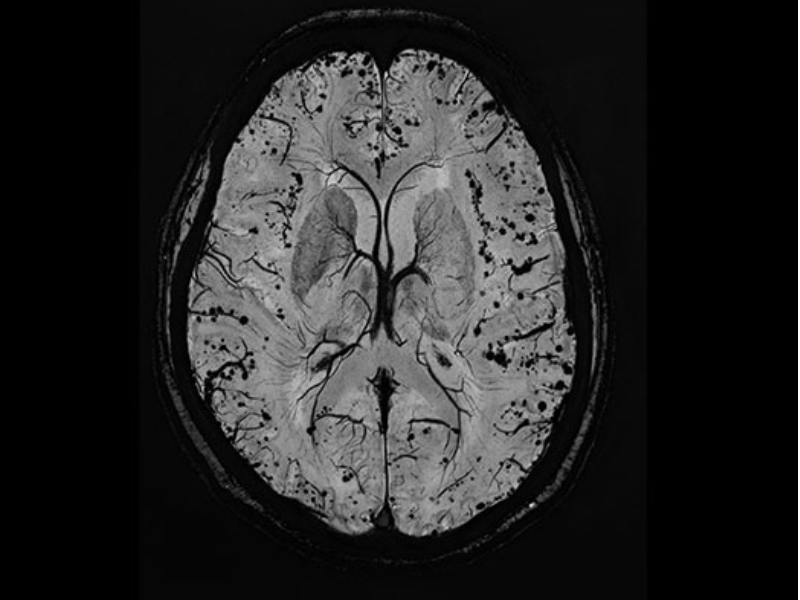

Axial SWI of the head